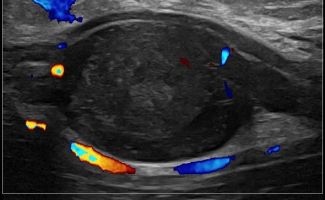

- Focal Lesions (tumors, neuromas)